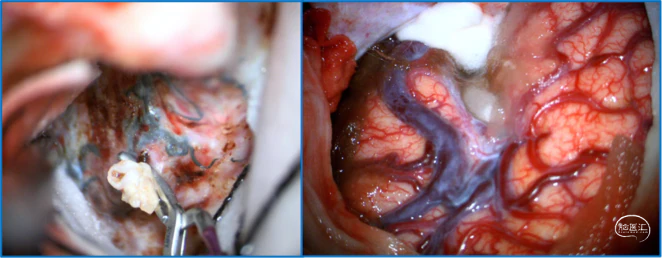

典型病例

![]()

神经内镜可以辅助确认颞极深部的引流静脉,避免残留引流静脉。